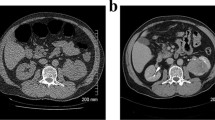

A Incidental discovered adenocarcinoma at right lung base, B Indeterminate ovarian mass (white arrow), which was shown to be a fibroadenoma. Ovarian masses can lead to more additional imaging tests and surgeries.